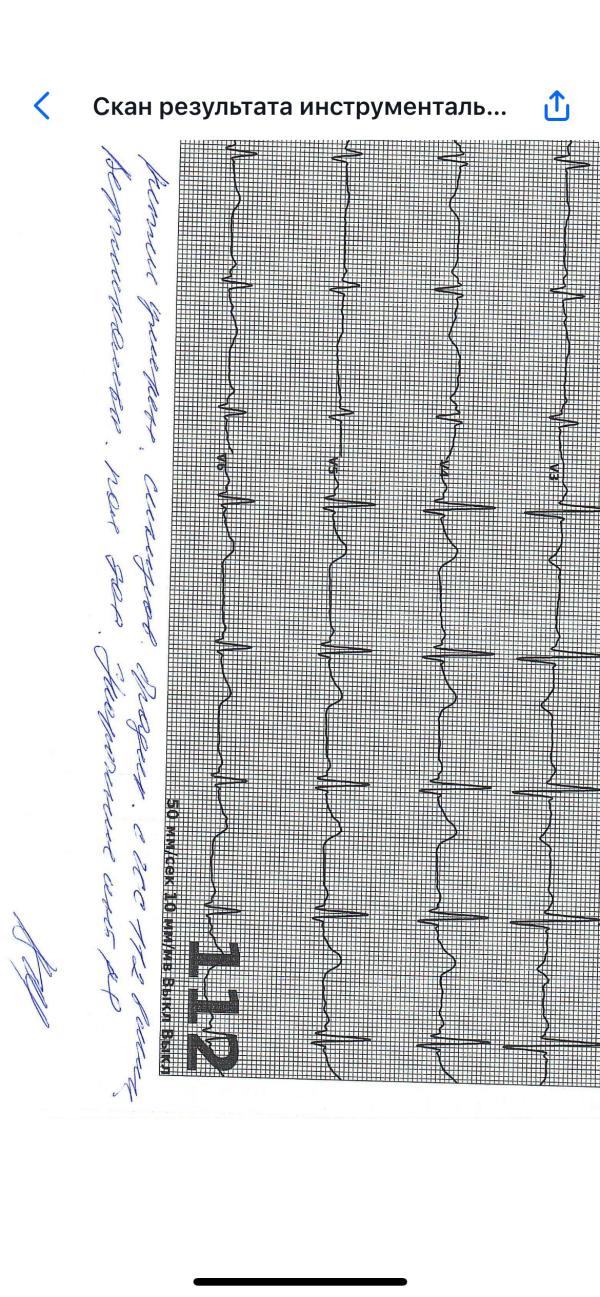

Кто-нибудь может расшифровать, что написано ?

…и в конце укорочение интервала…

Ритм умеренный, … , чсс 112 в мин

Вертикальное положение оси

Ритм умеренный синусовый, брадикардия пульс 112